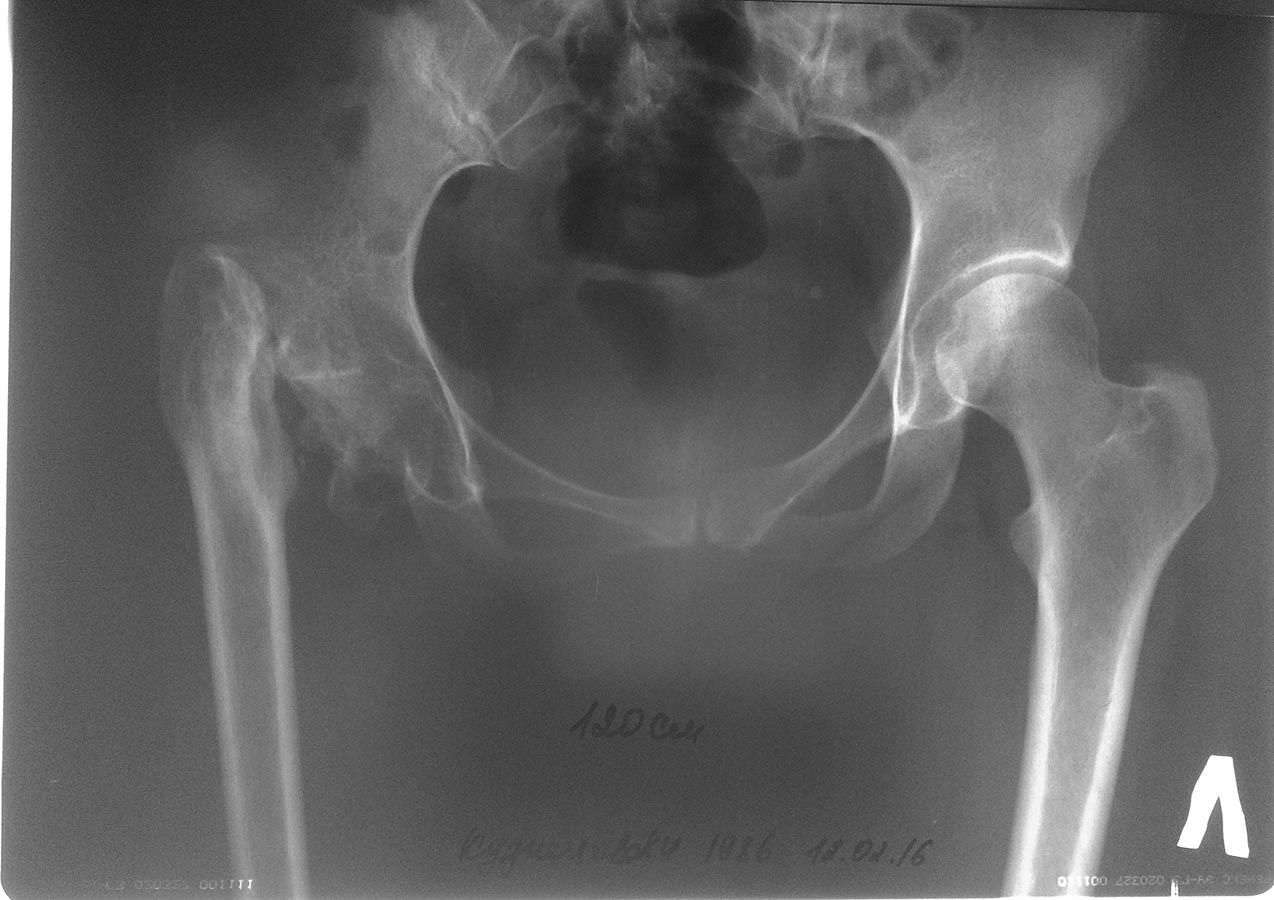

Re: Клинический разбор пациентки с ложным суставом шейки правой бедренной кости

Коллеги прошу прощения, технические неполадки. Вот первый снимок без нагрузки.

Обзорная рентгенография нижних конечностей.